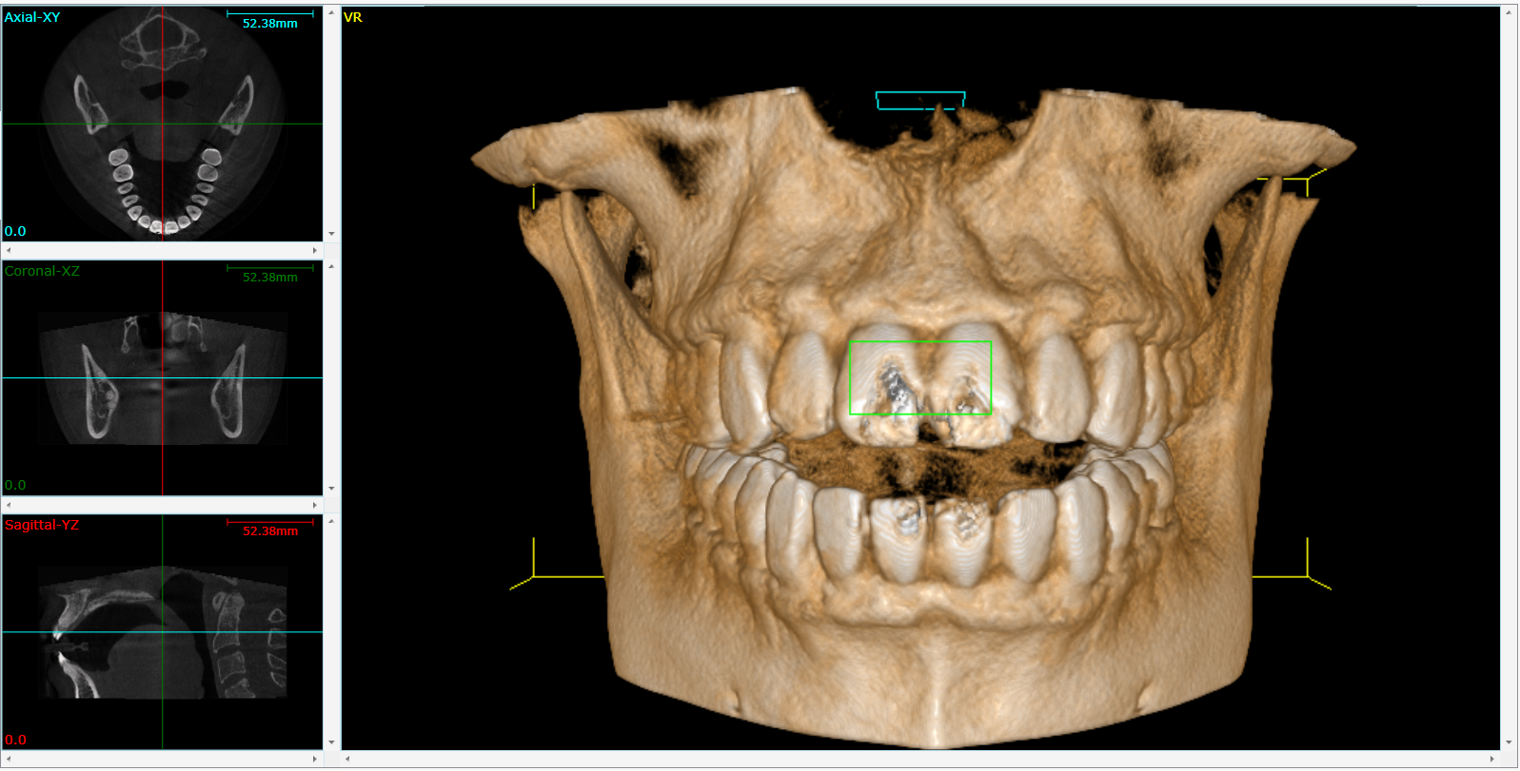

RIGENERAZIONE OSSEA GUIDATA

RIASSORBIMENTO OSSEO GRAVE

Radiografia panoramica che mostra un riassorbimento osseo alveolare diffuso secondario a parodontopatia cronica generalizzata.

La perdita ossea interessa prevalentemente le aree interprossimali, con riduzione dell’altezza crestale variabile, compatibile con una compromissione significativa del supporto parodontale.